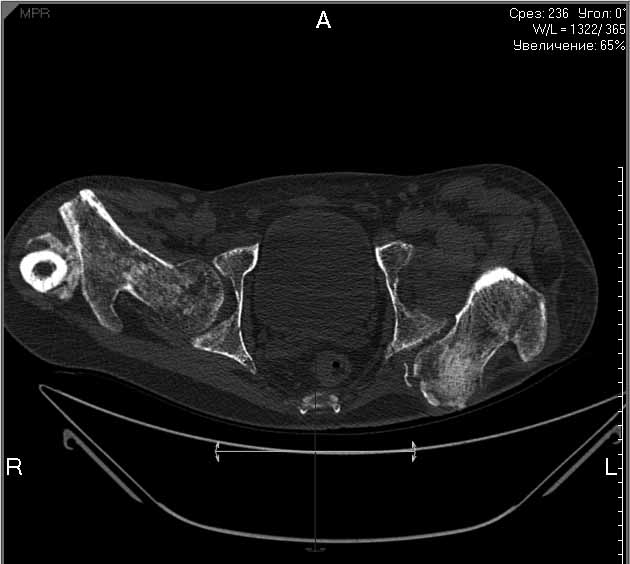

Пациенту 22 года. Травма в июле 2010г, лечился в районной больнице. К нам попал в апреле 2011г.Тяжелая сочетанная травма (29.07.2010): тупая травма живота с повреждением внутренних органов. Закрытая травма грудной клетки с переломом ребер. Пневмоторакс справа. Тяжёлая позвоночно-спинномозговая травма. Закрытый осложнённый переломо-вывих С5 позвонка. Верхний парапарез, нижняя параплегия, нарушение функции тазовых органов по типу недержания. Цекостома. Пролежень левой ягодичной области. Неправильно консолидированные переломы верхних третей обеих бедер. Застарелый вывих левого бедра.Осложнение: Поддиафрагамльный абсесс слева, забрюшинного пространства. Свищ желудка и ободочной кишки. Синегнойный сепсис. Двухстороняя пневмония. Но это уже анамнез.Пациент был неоднократно оперирован на органах брюшной полости и осложнениями с ними связанными.

В ягодичной области слева глубокий пролежень размером 2х2см, дном является вывихнутая головка бедра. Неврологически в нижних конечностях динамика положительная, появились движения в правой стопе, чувствительность в стопах.По переломам бедер: подвижности в местах переломов нет, снимки высылаю.

Планирую начать с правого бедра, ЧКО таза (передняя рама) с фиксацией бедра. О/клазия места перелома правого бедра и устранение грубых смещений в аппарате. окончательно можно оставить и в аппарате. Далее аппаратное устранение вывиха левого бедра.